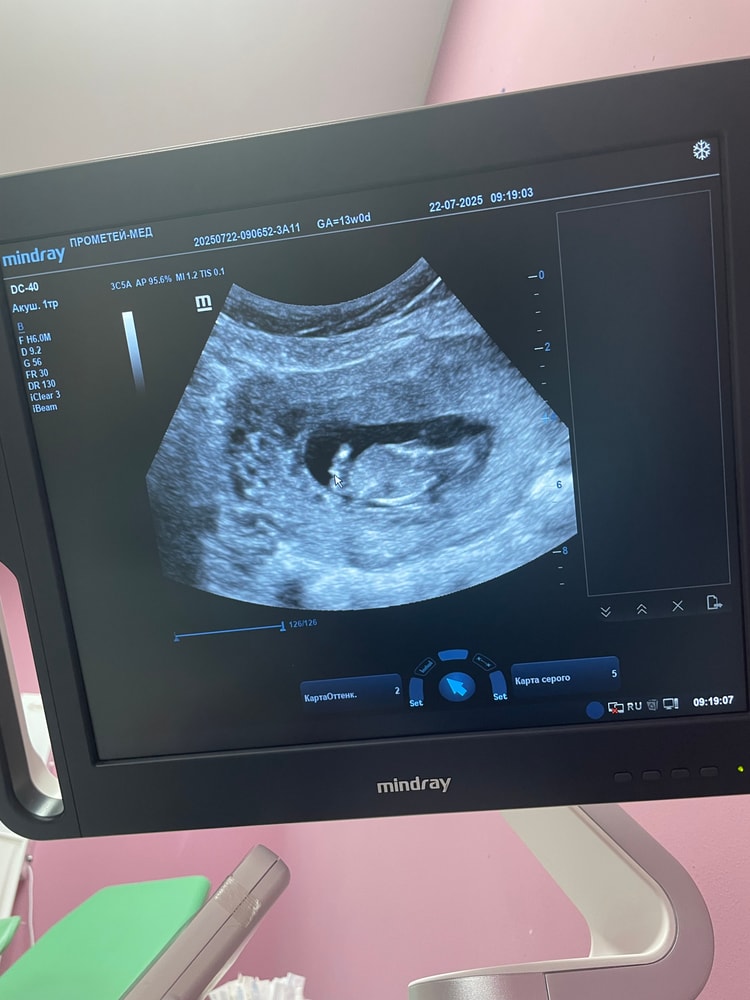

Вторая беременность, 37 лет. Первая была 5 лет назад. Все замечательно, низкие риск .

Пошли с мужем на первое узи. И слышу слова от которых немеет тело. Гипоплазия носа 1,6. Твп 2,9. Срок 11,6, по узи ставят 12,4.

завтра иду на повторное узи. Результаты крови через неделю придут. Постараюсь завтра сдать Нипт.